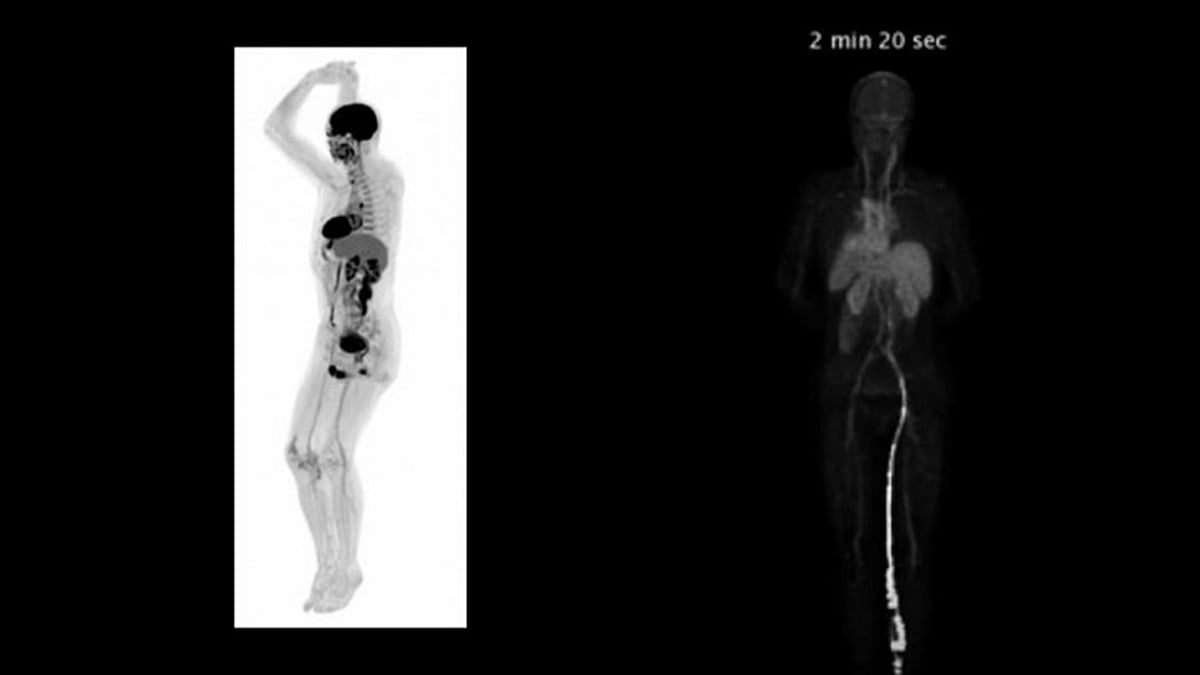

মানুষের রোগের চিকিৎসায় স্ক্যানিং প্রযুক্তি এখন হাতের নাগালে। কিন্তু পুরো শরীর নিমেষেই স্ক্যান করে থ্রিডি ছবি দেখাতে পারে—এমন যন্ত্র এত দিন ছিল না। সম্প্রতি বিশ্বের প্রথম মেডিকেল ইমেজিং স্ক্যানারে প্রথমবারের মতো স্ক্যান করে সফলতা পেয়েছেন মার্কিন বিশেষজ্ঞরা।

এ যন্ত্রের মাধ্যমে ২০ থেকে ৩০ সেকেন্ডেই পুরো শরীর স্ক্যান করা যায়। যন্ত্রটির নাম এক্সপ্লোরার।

এক্সপ্লোরার নামের স্ক্যানার যন্ত্রটিতে পজিট্রন এমিশন টমোগ্রাফি (পিইটি) ও এক্স-রে কম্পিউটেড টমোগ্রাফির (সিটি) সমন্বয়ে ৪০ গুণ দ্রুতগতিতে ছবি পাওয়া যায়। অন্যান্য স্ক্যানারের তুলনায় দূর থেকে রেডিয়েশন ধরতে পারে।

গবেষক র্যামসে বাদাওয়ি বলেন, ছবিতে যে ডিটেইল পাওয়া যায়, তা চমক দেওয়ার মতোই। প্রচলিত পিইটি স্ক্যানে যেসব ছবি পাওয়া যায় না এতে তাও ধরা সম্ভব। মানুষের ক্ষেত্রে যে ধরনের তথ্য প্রয়োজন হয়, অন্য যন্ত্রে তা এতটা বিস্তারিত পাওয়া সম্ভব নয়।

গবেষক চেরি বলেন, এক্সপ্লোরার চিকিৎসা ক্ষেত্রে ও রোগ নির্ণয়ে দারুণ প্রভাব ফেলবে। অঙ্গপ্রত্যঙ্গ ও কোষে কী ঘটছে, এ স্ক্যানারের ছবিতে তা ধরা পড়বে। শরীরে কোন অংশে কতটুকু গ্লুকোজ যাচ্ছে বা রক্তপ্রবাহের বিষয়টিও মাপা যাবে।